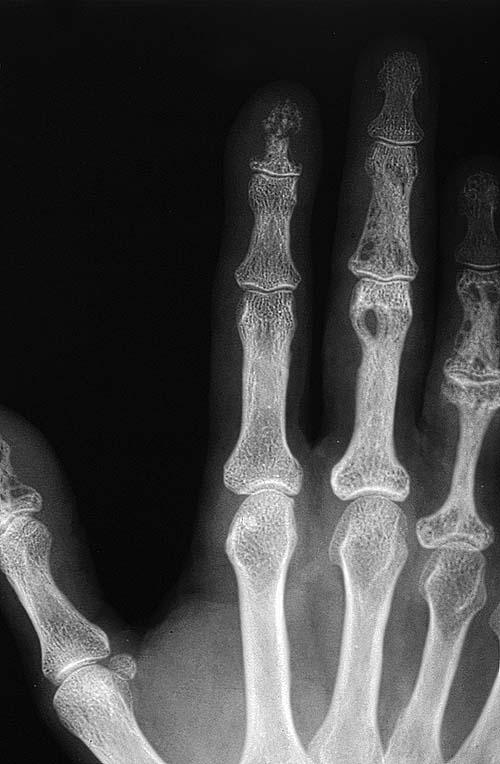

Sarcoidosis = الساركوئيد